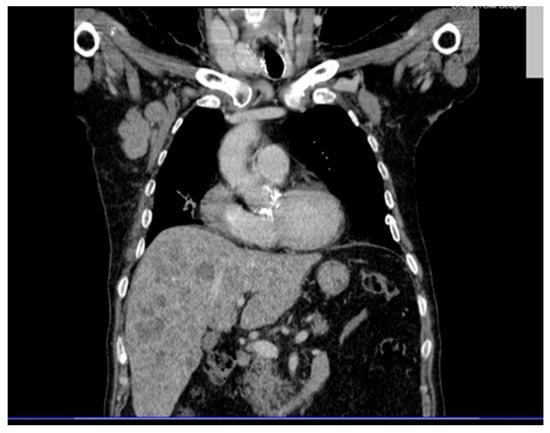

Background and Clinical Significance: Merkel cell carcinoma (MCC) is a rare, aggressive neuroendocrine cutaneous malignancy with increasing incidence among elderly, immunocompromised patients or individuals exposed to ultraviolet radiation. Case Presentation: We present the case of an 84-year-old Caucasian male with no history of [...] Read more.

Background and Clinical Significance: Merkel cell carcinoma (MCC) is a rare, aggressive neuroendocrine cutaneous malignancy with increasing incidence among elderly, immunocompromised patients or individuals exposed to ultraviolet radiation. Case Presentation: We present the case of an 84-year-old Caucasian male with no history of immunosuppression, who was admitted for asthenia, dysphagia, weight loss, and generalized weakness. Clinical and imaging investigations revealed a violaceous tumor on the right arm and disseminated metastases affecting the liver, spleen, bones and lymph nodes. A liver biopsy confirmed a small round blue cell neoplasm suggestive for MCC, although immunohistochemistry could not be performed due to the patient’s fulminant deterioration and death within 12 days of admission. Conclusions: This case is notable for its exceptionally rapid progression, particularly splenic involvement, and absence of known immunosuppressive factors. It highlights the existence of highly proliferative MCC subtypes with potential for bypassing classical metastatic pathways. Early clinical suspicion and prompt histological evaluation are essential for diagnosis, although the prognosis remains poor in advanced stages. Due to fulminant deterioration, immunohistochemistry could not be performed; therefore, the diagnosis is highly suggestive based on clinical, imaging, and morphological correlation. Full article